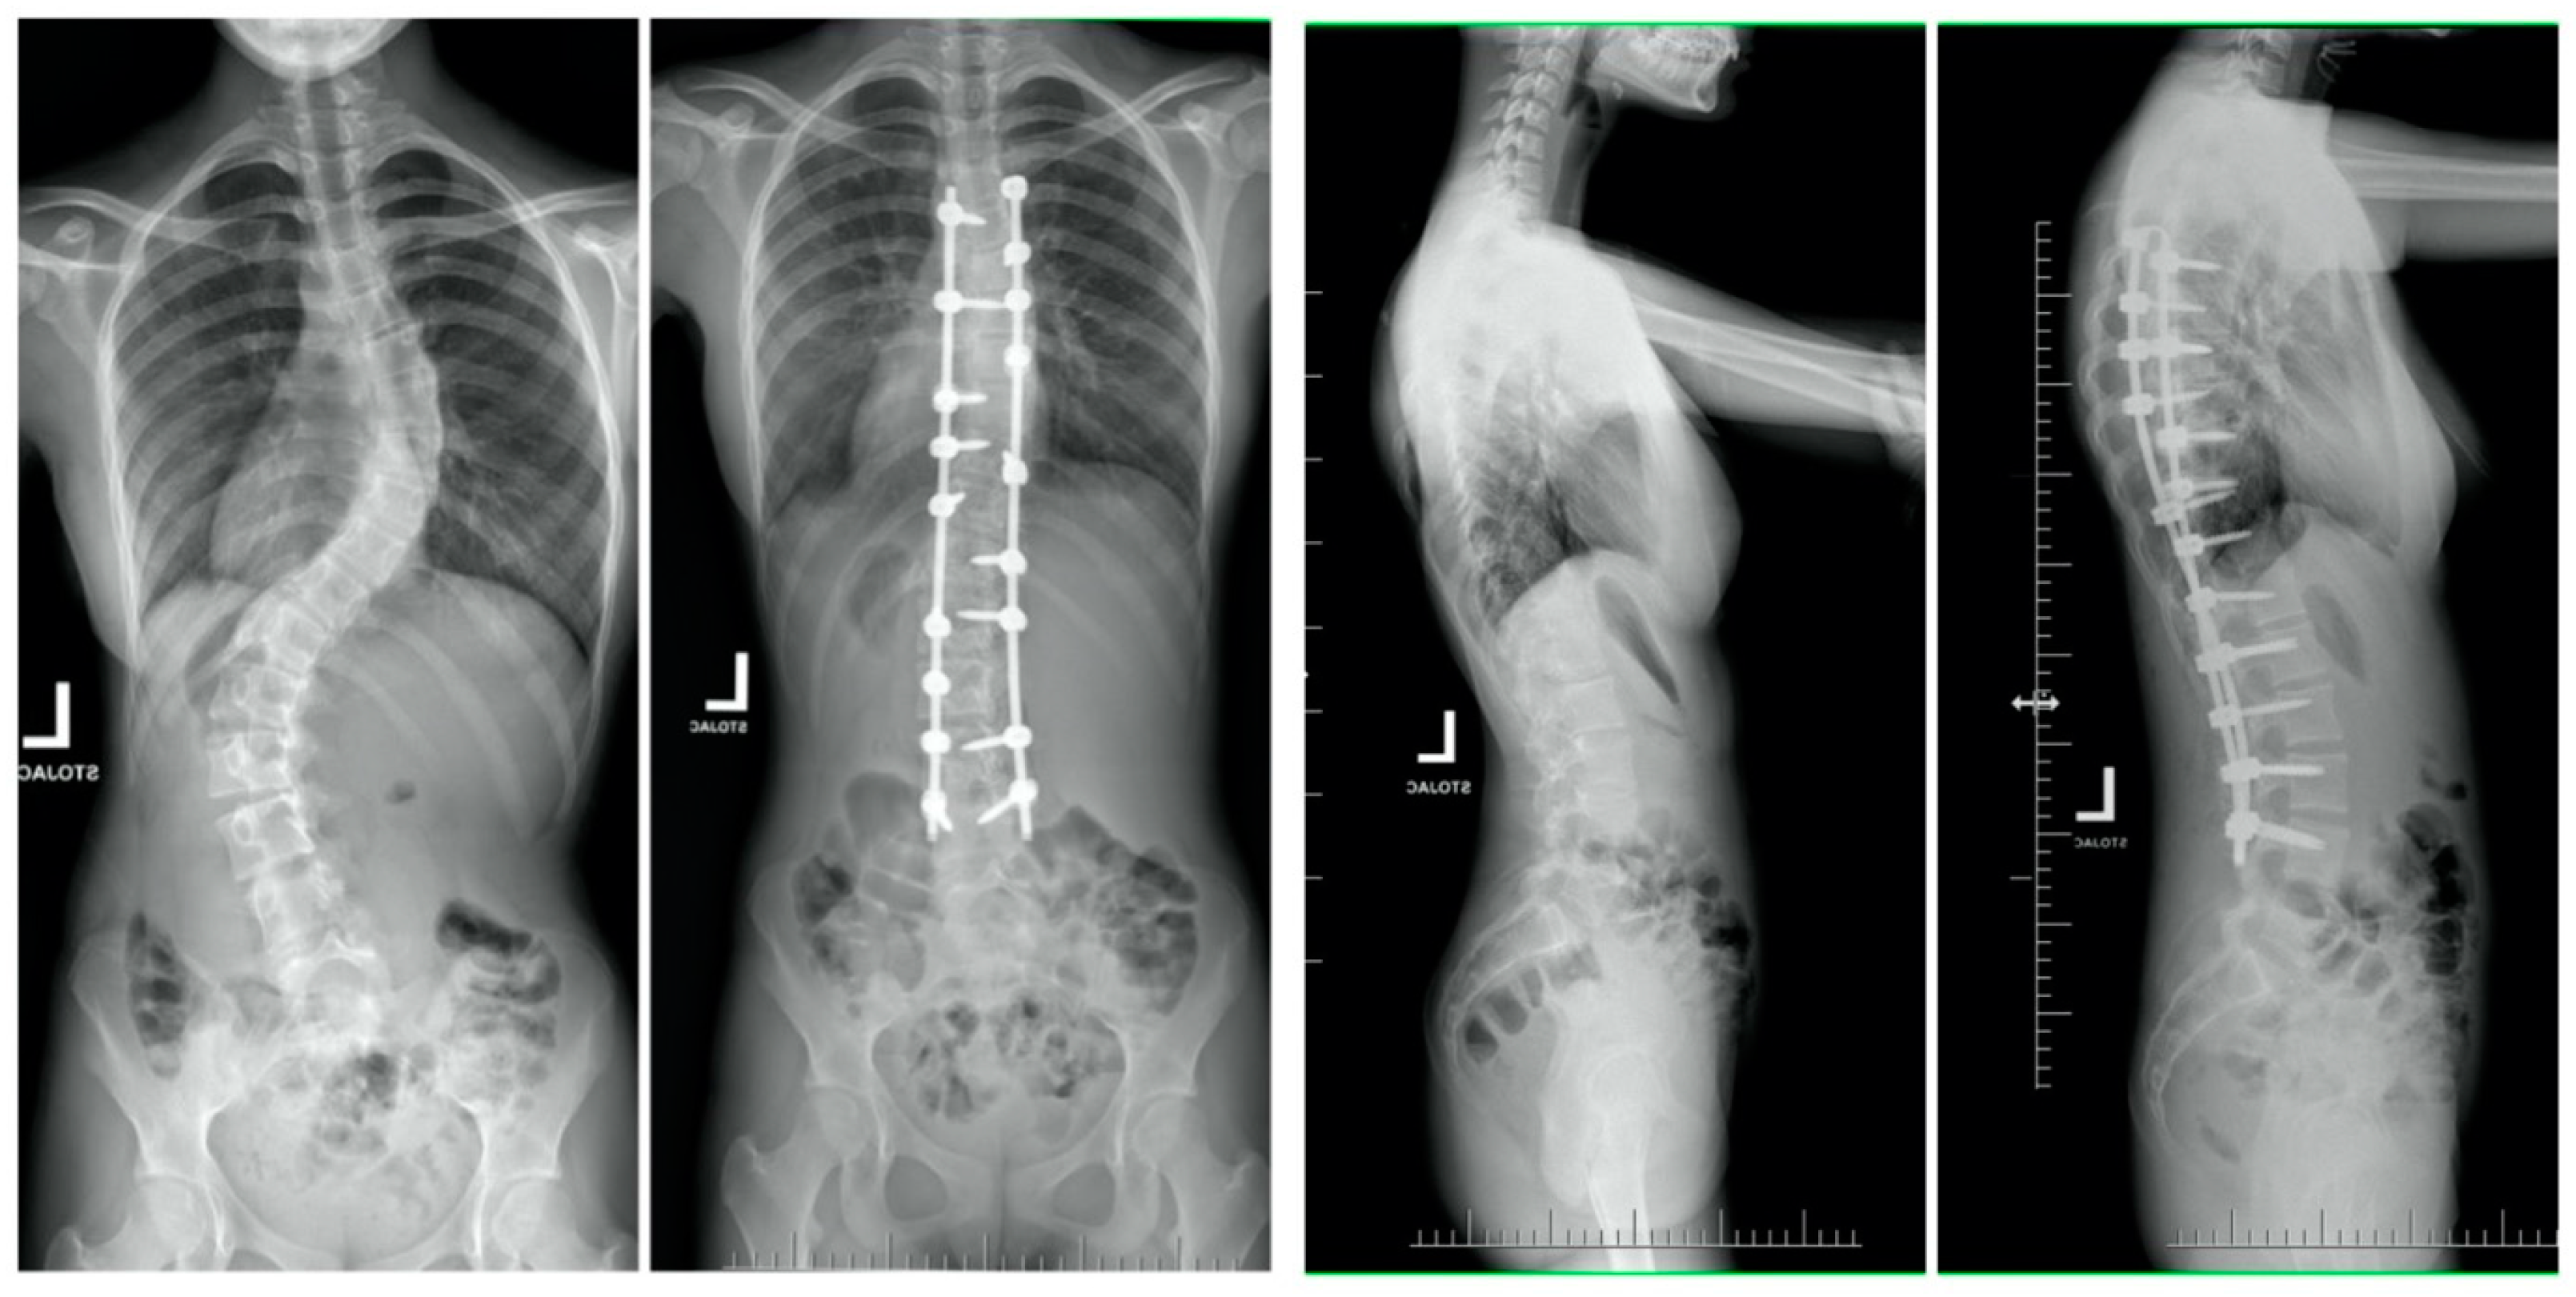

| Mean (SD) preoperative Cobb, deg | 131 (13.8) | 60 (9.5) | <0.001 |

| Mean (SD) Cobb at final follow-up, deg p-value * (pre vs. follow-up) | 61 (19.2) | 18 (9.2) | <0.001 |

| Mean (SD) preoperative thoracic kyphosis T5-T12, deg | 83 (35.9) | 25 (14.2) | <0.001 |

| Mean (SD) thoracic kyphosis T5-T12 at final follow-up, deg p-value * (pre vs. follow-up) | 35 (9.6) | 22 (8.2) | 0.24 |

| Mean (SD) preoperative forced vital capacity, percentage of predicted | 51.2 (12.8) | 83 (11.2) | <0.001 |

| Mean (SD) forced vital capacity, percentage of predicted at final follow-up p-value * (pre vs. follow-up) | 69.9 (11.2) | 79 (13.2) | 0.486 |